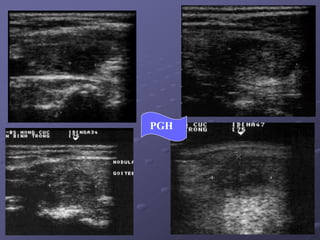

PGH

VOÂI HOAÙ / PGH